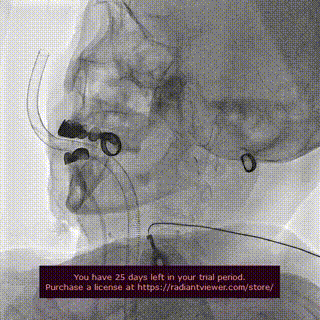

患者主动脉瓣呈TYPE0型二叶瓣,重度钙化,法式窦结构不大,双冠高度可,升主动脉未见明显增宽,心脏角度约69°,心肌肥厚,考虑到术中斑块脱落导致的卒中的风险,选择颈内动脉先行植入Emboshield Nav6抗栓塞远端保护装置进行保护,再行TAVR术。

左颈动脉放入脑保护伞

脑保护伞回收